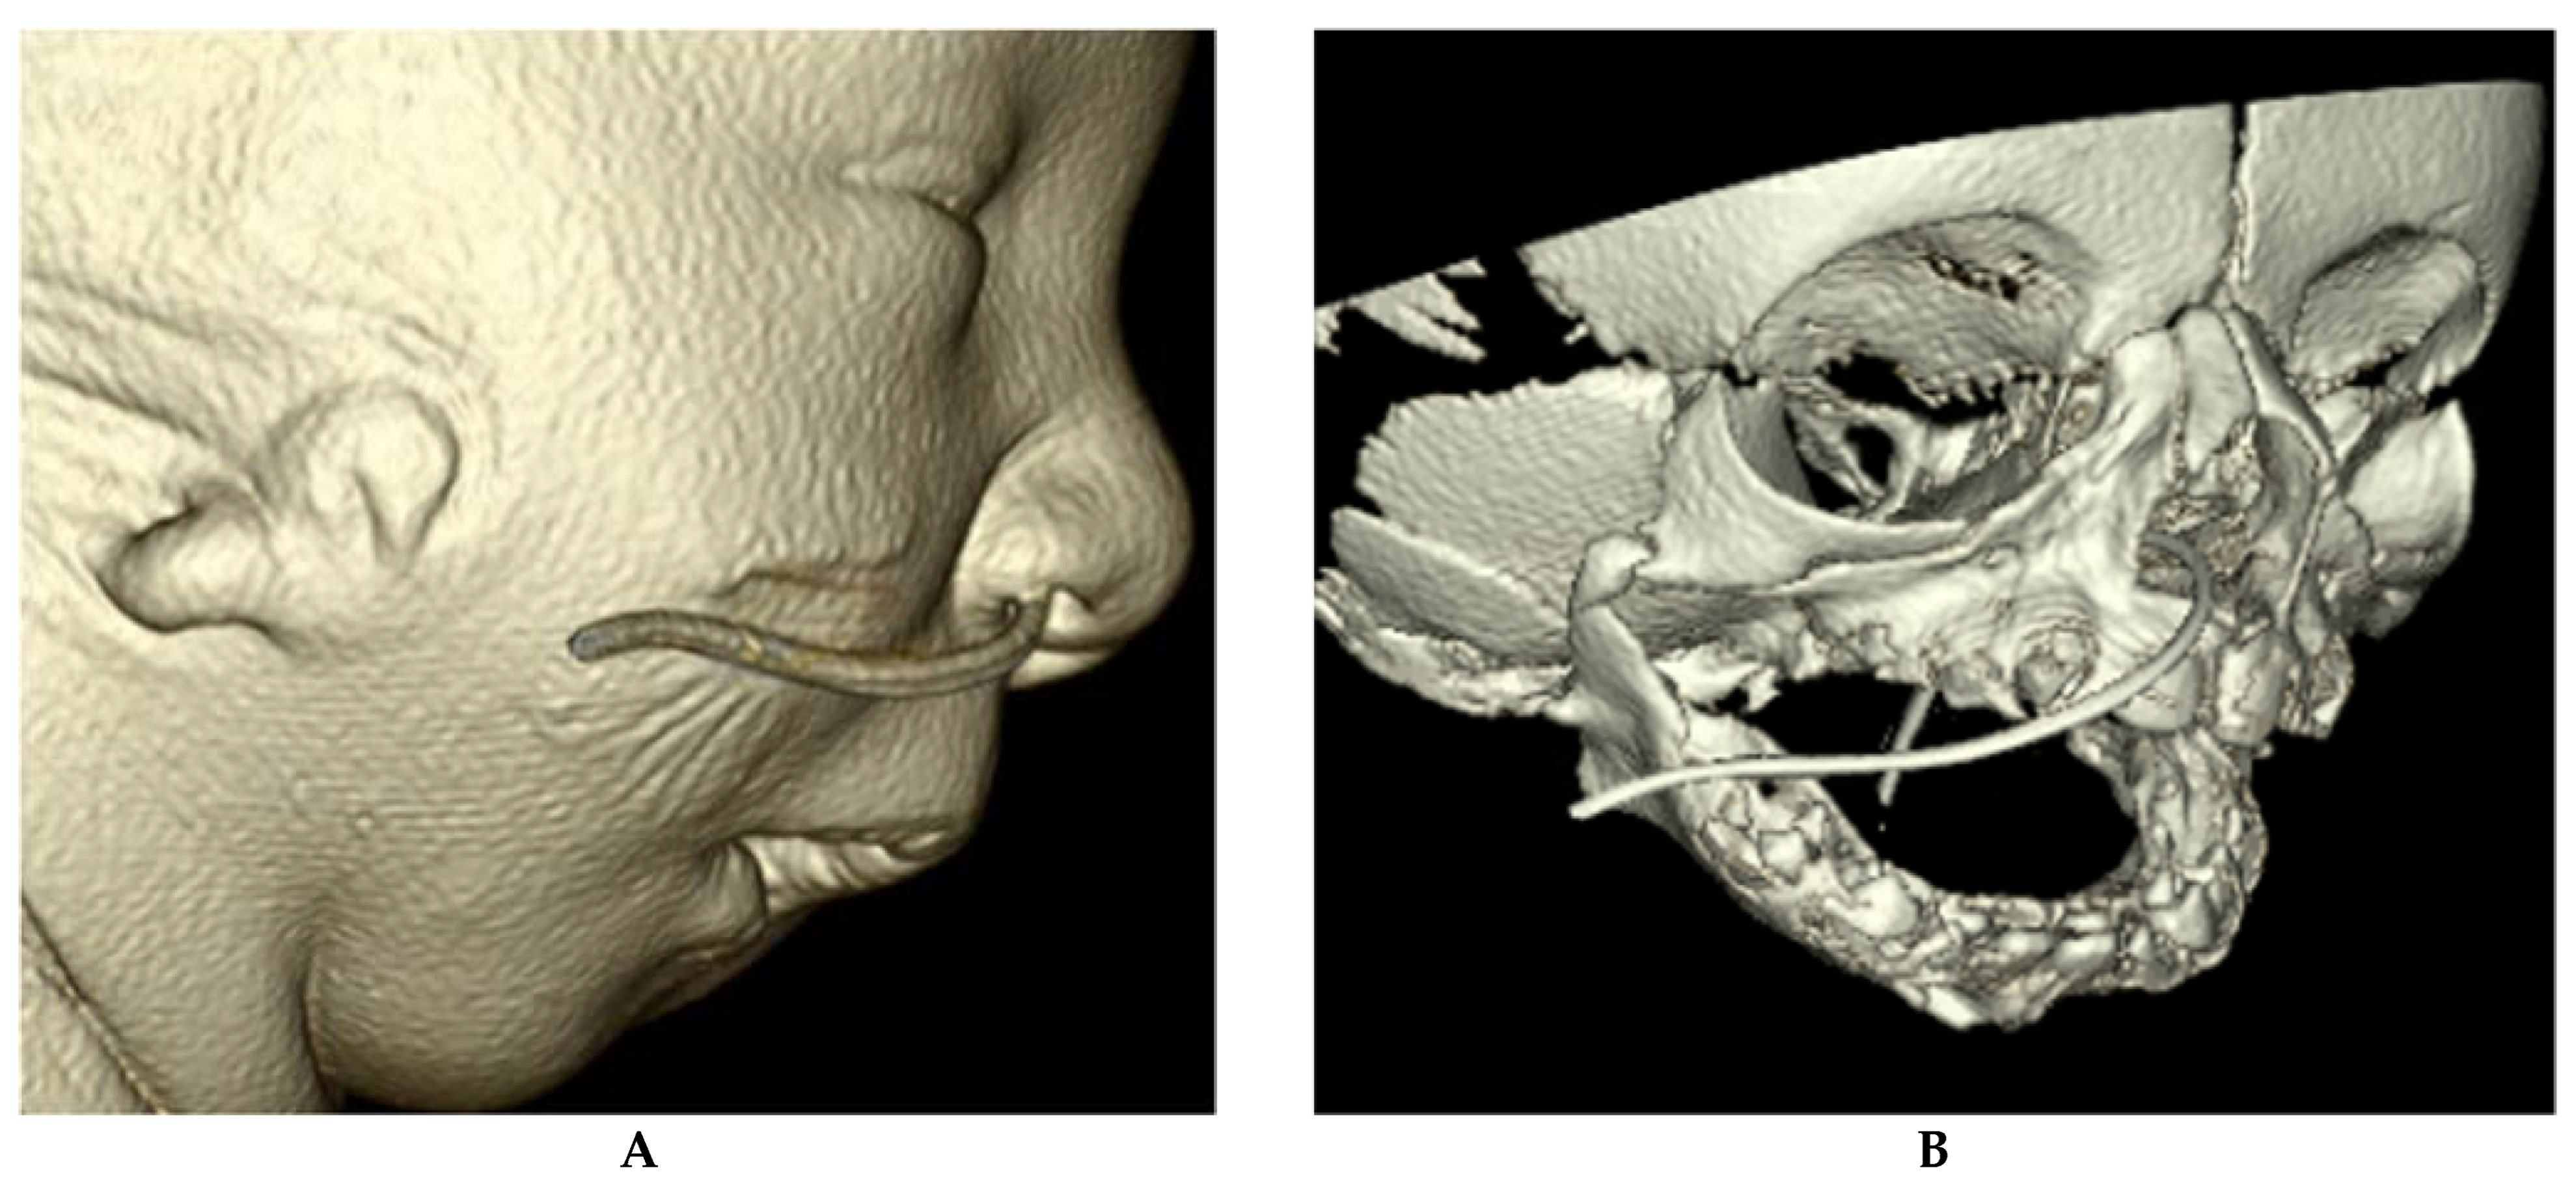

2.12.1. Congenital Nasal Pyriform Aperture Stenosis

- Shah, G.B.; Ordemann, A.; Daram, S.; Roman, E.; Booth, T.; Johnson, R.; Xi, Y.; Mitchell, R. Congenital nasal pyriform aperture stenosis: Analysis of twenty cases at a single institution. Int. J. Pediatr. Otorhinolaryngol. 2019, 126, 109608. [Google Scholar] [CrossRef]

- Sesenna, E.; Leporati, M.; Brevi, B.; Oretti, G.; Ferri, A. Congenital nasal pyriform aperture stenosis: Diagnosis and management. Ital. J. Pediatr. 2012, 38, 28. [Google Scholar] [CrossRef] [PubMed] [Green Version]

- Losken, A.; Burstein, F.D.; Williams, J.K. Congenital nasal pyriform aperture stenosis: Diagnosis and treatment. Plast. Reconstr. Surg. 2002, 109, 1506–1511, discussion 1512. [Google Scholar] [CrossRef] [PubMed]